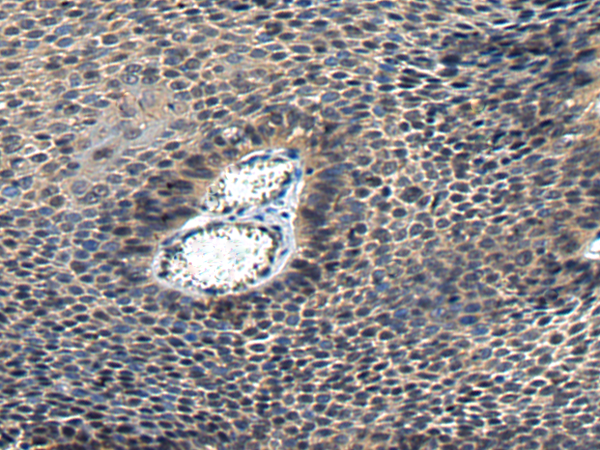

分类: 科研抗体货号: P05789别名: HOX1; HOX1E应用: IHC反应种属: Human, Mouse